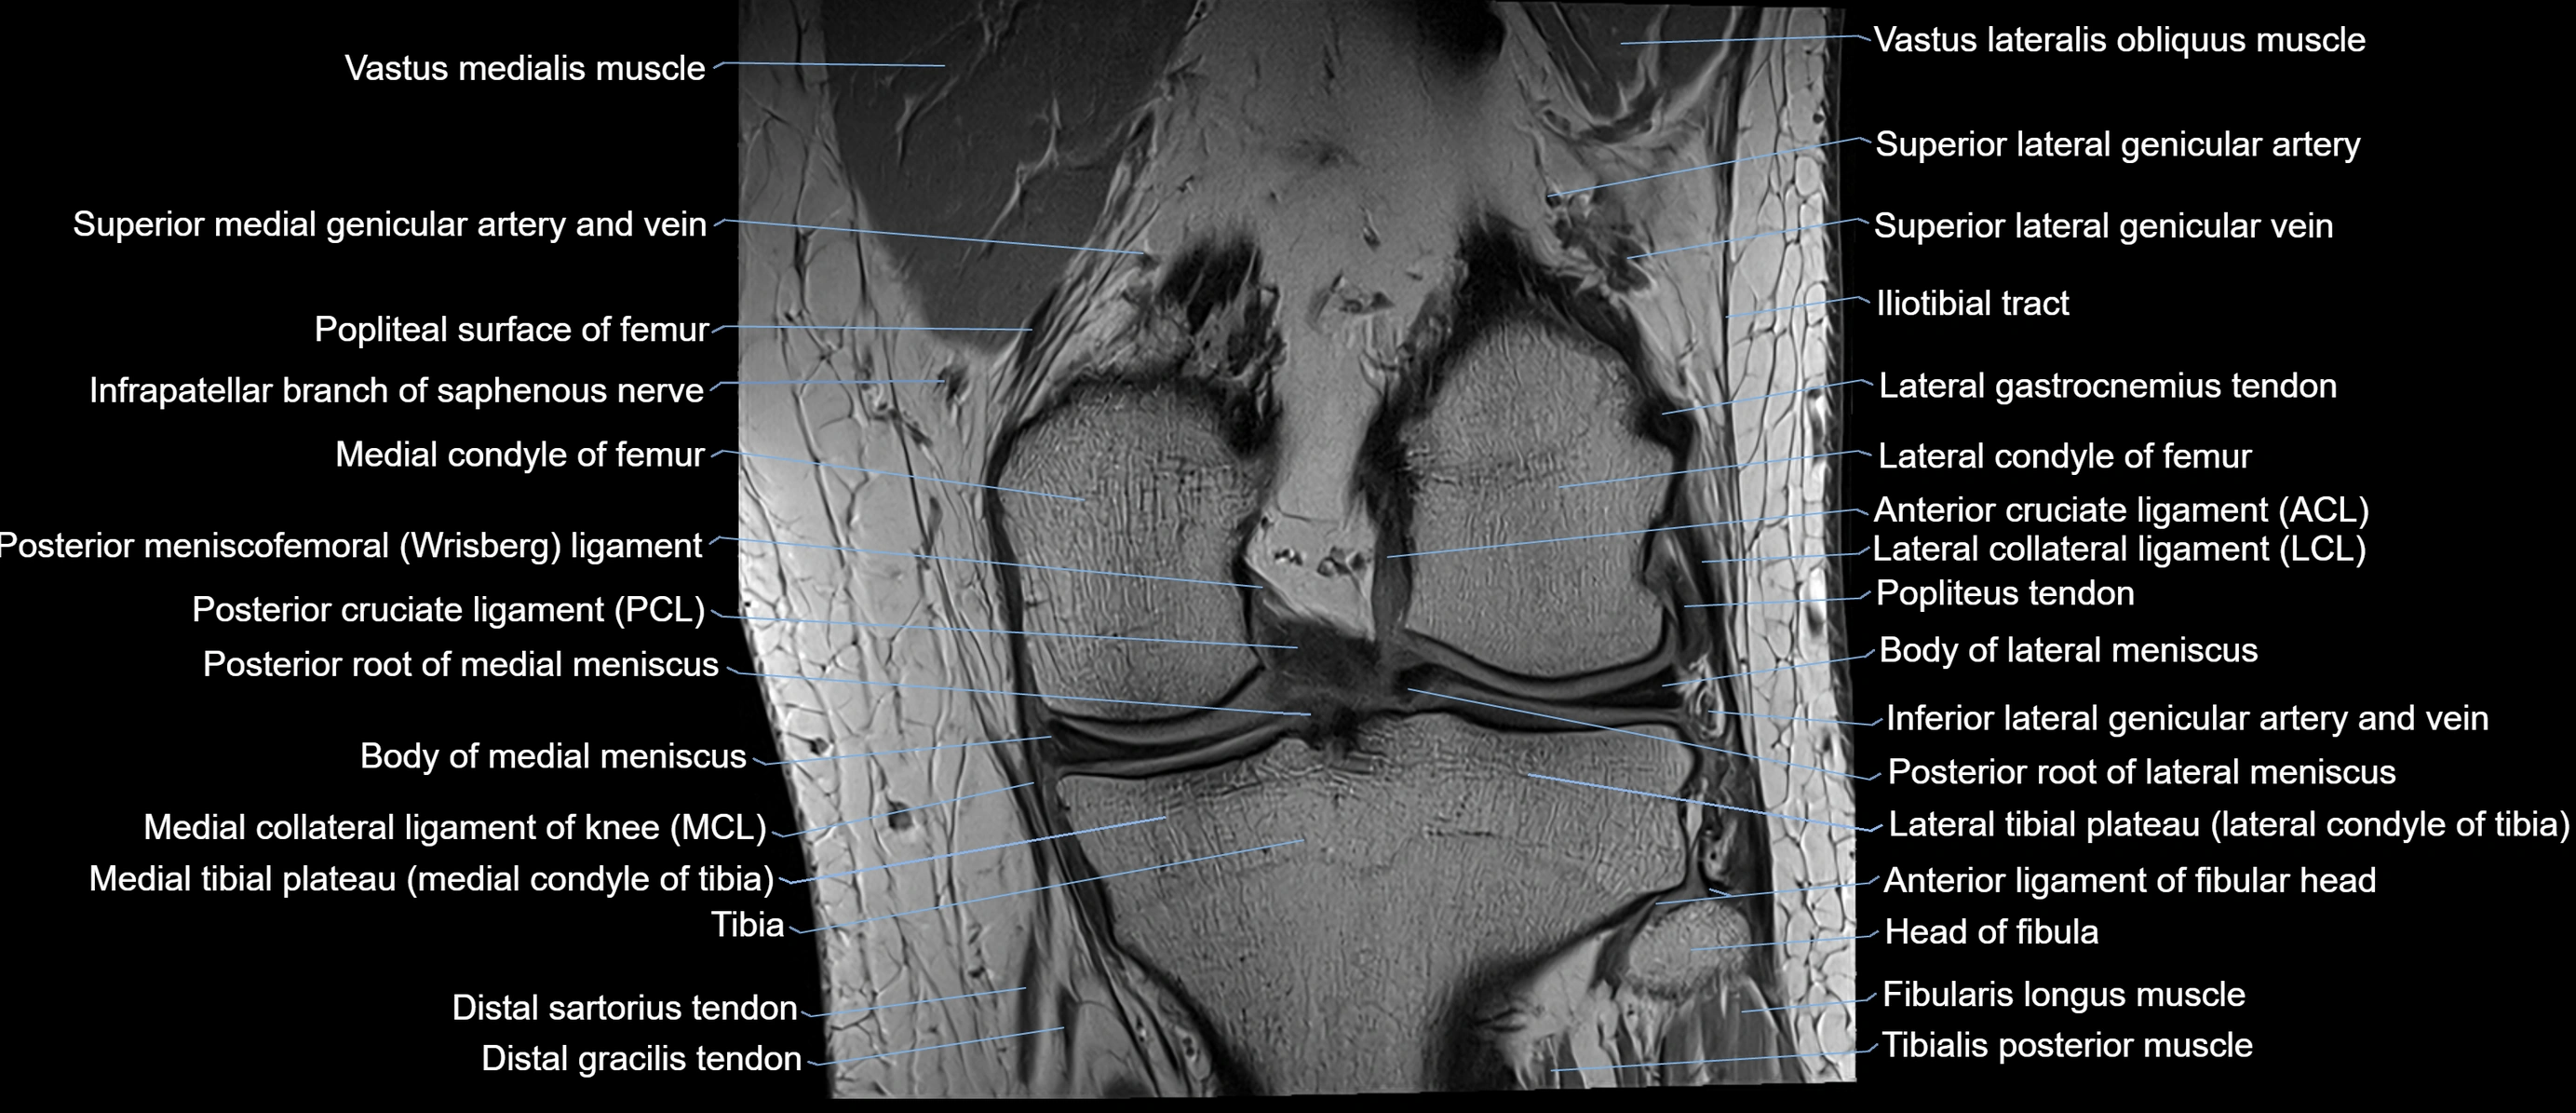

- Posterior cruciate ligament

- Posterior meniscofemoral ligament

- Lateral collateral ligament

- Medial collateral ligament

- Body of lateral meniscus

- Body of medial meniscus

- Posterior root of lateral meniscus

- Posterior root of medial meniscus

- Lateral gastrocnemius tendon

- Popliteus tendon

- Head of fibula

- Anterior ligament of fibular head

- Fibularis longus muscle (peroneus longus muscle)

- Popliteus muscle